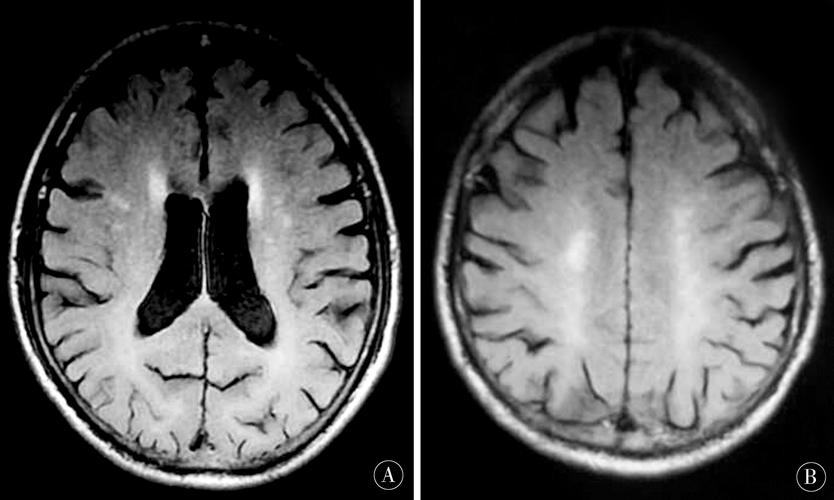

腔隙性脑梗mri表现

(图片来源网络,侵删)

• DWI:病灶仍呈明显高信号,弥散受限达到顶峰。

• ADC:持续呈低信号

• T2加权像:病灶开始出现高信号

• FLAIR(液体衰减反转恢复)序列:对显示靠近脑脊液(如脑室、脑沟)的病灶非常敏感,病灶呈明显高信号,且比T2更清晰,因为脑脊液信号被抑制了。

• T1加权像:病灶通常呈等信号或低信号,此时可能不明显。

小结:急性期,DWI高信号T2/FLAIR高信号是主要表现。